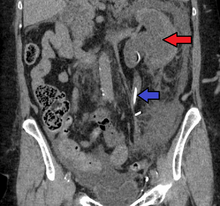

Imaging studies, such as an intravenous urogram (IVU), ultrasound, CT or MRI, are also important investigations in determining the presence and/ or cause of hydronephrosis. Whilst ultrasound allows for visualisation of the ureters and kidneys (and determine the presence of hydronephrosis and / or hydroureter), an IVU is useful for assessing the anatomical location of the obstruction. Antegrade or retrograde pyelography will show similar findings to an IVU but offer a therapeutic option as well. Real-time ultrasounds and color-flow Doppler tests in association with vascular resistance testing helps determine how a given obstruction is effecting urinary functionality in hydronephrotic patients.[12]

The choice of imaging depends on the clinical presentation (history, symptoms and examination findings). In the case of renal colic (one sided loin pain usually accompanied by a trace of blood in the urine) the initial investigation is usually a spiral or helical CT scan. This has the advantage of showing whether there is any obstruction of flow of urine causing hydronephrosis as well as demonstrating the function of the other kidney. Many stones are not visible on plain X-ray or IVU but 99% of stones are visible on CT and therefore CT is becoming a common choice of initial investigation. CT is not used however, when there is a reason to avoid radiation exposure, e.g. in pregnancy.